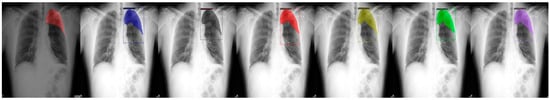

Figure 4.

From left to right: Ground Truth, ResNet50 (COCO), ResNet101 (COCO), ResNeXt101 (COCO), ResNet50 (LVIS), ResNet101 (LVIS), and ResNeXt101 (LVIS). This patient had pneumothorax in their top-left chest.

We chose a few examples to demonstrate the capabilities of various models. These images consisted of X-ray images of pneumothorax patients with different areas of disease inflicted. The inclusion of multiple positions and areas in the figures lets us observe the possible outcomes and the differences between the models. In Figure 3 and Figure 6, the patients had pneumothorax on the right side of their chest, with the patient in Figure 6 only affecting the top part, while the patient in Figure 3 had pneumothorax on the outside wall of their right lung. In Figure 4, Figure 5 and Figure 7, the patients had pneumothorax in the left side of their chest, while the patients in Figure 4 and Figure 5 had the upper part of their left lung mostly collapsed, indicating a serious issue of pneumothorax disease. In Figure 5, there are cavity areas at the bottom part, too. In the same image, the ground truth included a portion protruding below the area of the top detection portion due to the late-stage pneumothorax with most of the upper part of the lung collapsing, and all models were unable to detect the cavity of the protruded part. In Figure 7, the patient is seen with a fixation, with the pneumothorax affecting the top left lung, albeit with a smaller area.